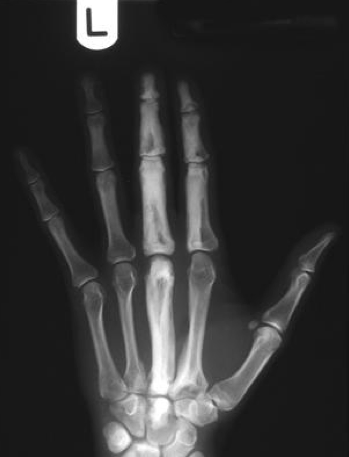

Findings and diagnosis?

metaphyseal cupping and fraying in the distal radius and ulna

Ricketts